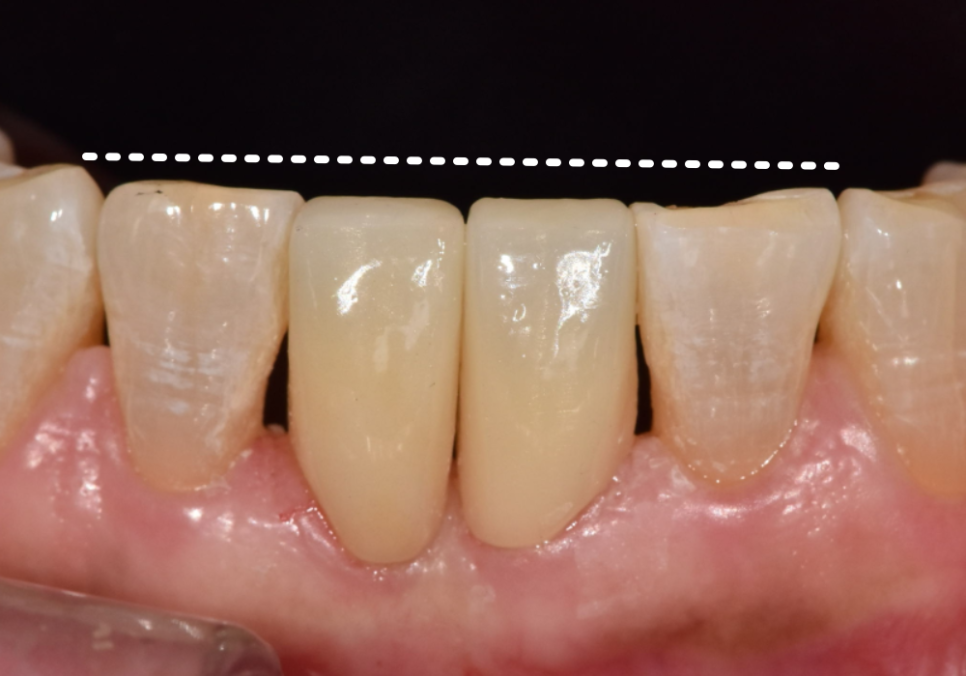

결과적으로 환자분께

가장 만족스러운 대안이 되었습니다.

살짝 틀어져 있던 앞니가 제 자리를 찾고 나니,

미소가 훨씬 단정하고 편안해 보이시죠?